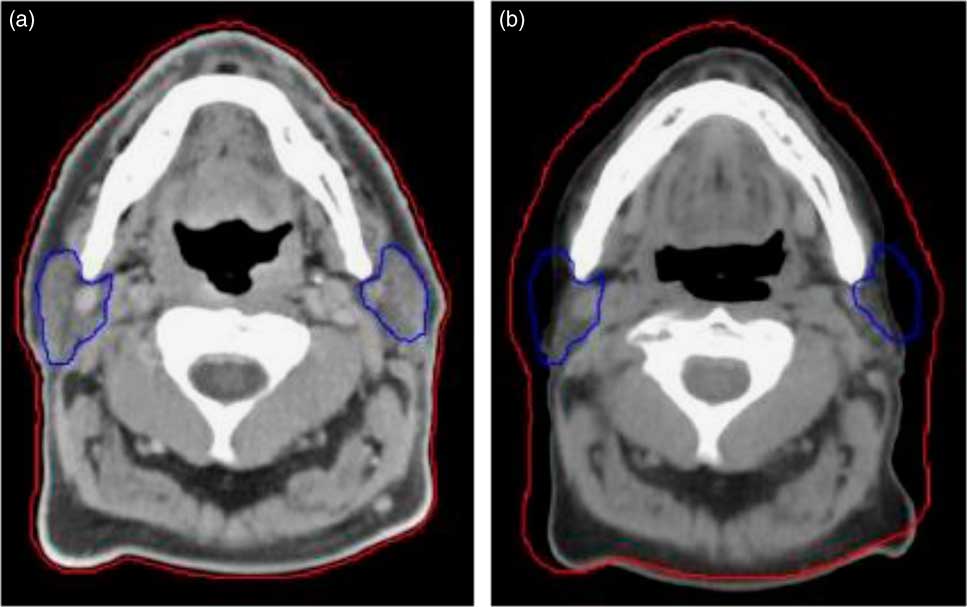

1. Patients who were likely to have tumour shrinkage due to response and weight loss at 20th fraction (usually in head and neck patients the weight loss or tumour shrinkage occurs in 4th week of the treatment fraction) in the course of radiotherapyReference Wang, Yang and Hu 8 (Figure 1).

Figure 1 Compared to the planning CT (a), a rescan at 20th fraction (mid-way) through treatment (b) highlights weight loss and changes to the parotids. The external contour is shown by the red line and the parotids by the blue line.